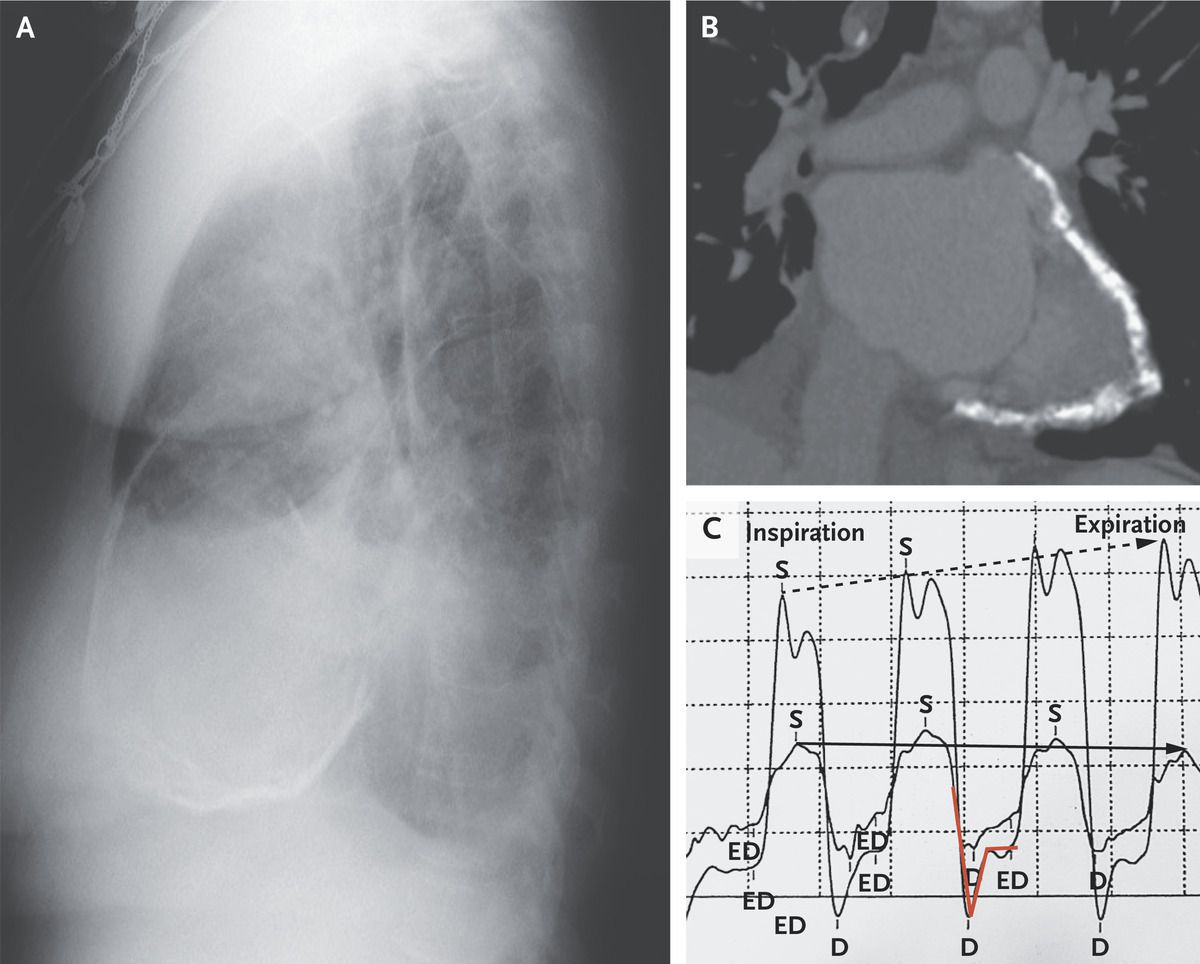

A 69-year-old woman presented to the emergency department with a 3-year history of dyspnea on exertion. She had a history of focal pleural plaques that had been attributed to asbestos exposure that occurred during her work at an insulation-manufacturing company. Physical examination was notable for signs of volume overload. A chest radiograph showed circumferential calcification of the pericardium, pleural effusions, and interstitial edema (Panel A, lateral view). Computed tomography of the chest revealed extensive pericardial calcification (Panel B). A transthoracic echocardiogram showed a preserved ejection fraction with a septal bounce in early diastole as well as expiratory diastolic reversal in the hepatic vein. A subsequent simultaneous left and right heart catheterization showed ventricular interdependence and discordance of the pressure tracings. During inspiration, when pressures in the right ventricle were at their highest, left ventricular pressures were at their lowest; this pattern reversed during expiration (Panel C; right ventricular pressure, solid arrow; left ventricular pressure, dotted arrow). A “square root” sign (also called a dip-and-plateau pattern; Panel C, red line), which represents rapid ventricular filling in early diastole before abrupt cessation in late diastole, was seen. A diagnosis of constrictive pericarditis due to asbestosis was made. A pericardiectomy was performed. Analysis of pericardial tissue was negative for tuberculosis. At 2 years of follow-up, the patient was doing well.